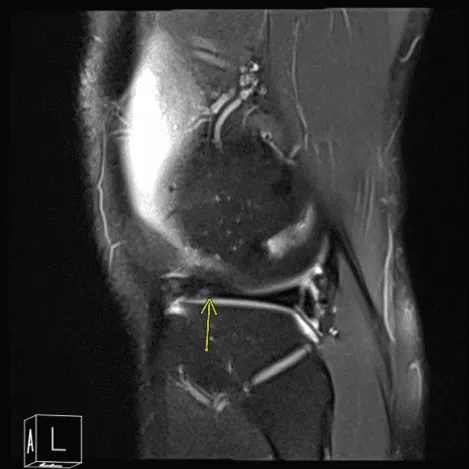

Patient requested to come back to the office with an MRI result. MRI impression as follows: Postsurgical changes of the lateral meniscus with mild recurrent tearing of the body segment and anterior horn however the appearance is improved compared to the presurgical study. Parameniscal cyst formation has resolved.

MRI of the right knee

MRI of his right knee was presented and clearly showed that there is tearing of the lateral meniscus anterior horn with parameniscal cyst tracking into the anterior intercondylar notch adjacent to the anterior root attachment site measuring 2 x 2.3 x 0.8 cm. Trace right knee joint effusion.